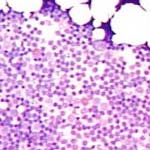

Zuerst wird das Knochenmark bei 100-facher Vergrösserung betrachtet (10er Okkular). Hier kann der Zellgehalt des Knochenmarks erfasst werden. Die Zellularität ist altersabhängig und kann als grobe Faustregel als 100% minus Alter berechnet werden. Der Rest besteht aus Fettvakuolen. Weiter lassen sich lokale Zellansammlungen, z.B. Lymphfollikel erkennen. Die dunklen Haufen entsprechen Knochenmarkbröckeln. Die Megakaryozyten sind schon bei dieser Vergrösserung erkennbar (gelbe Kreise).

Bei 400-facher Vergrösserung sind die meisten Zellen identifizierbar. Normalerweise bietet sich ein buntes Bild. Das Verhältnis Myelopoiese (genauer Granulopoiese) zu Erythropoiese beträgt rund 3-4 zu 1. In den Knochenmarkbröckeln sind die Zellen sehr dicht gelagert und darum nicht beurteilbar. Einzig die Mastzellen (Gewebsbasophile) stechen als dunkle Flecken hervor.